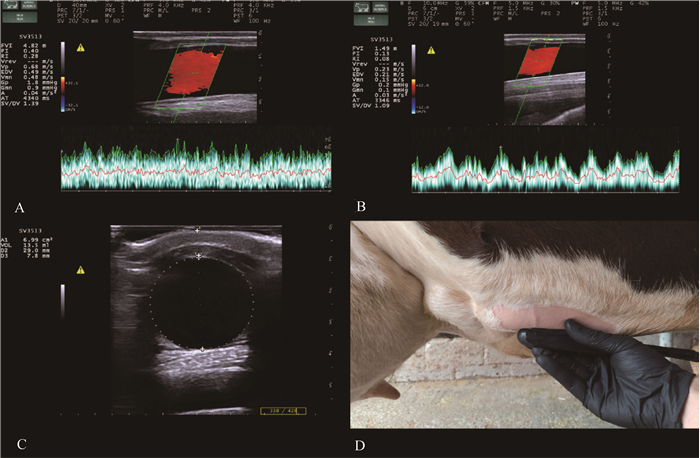

Mammary vein frequency Doppler examination of cows[75] A. Blood flow characteristics of the mammary veins of cows on day 14 of lactation; B. Blood flow characteristics of the mammary veins of cows on day 35 of dry milking; C. Distance, diameter, and cross-sectional area of the mammary veins from the surface of the skin; D. Mammary localization position of the Doppler imaging probe"